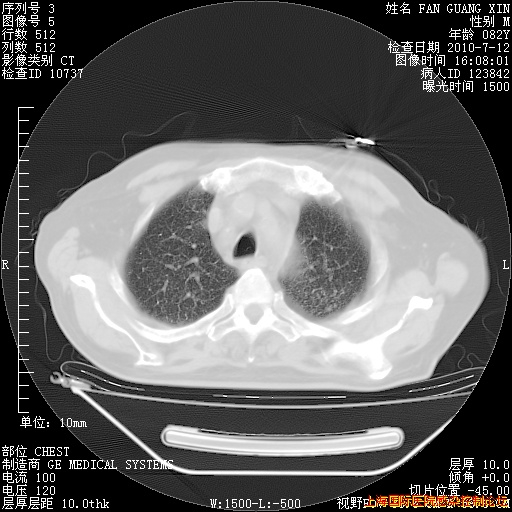

今天复查CT

今天CT

整整相隔30天的肺部CT好像有所好转啊。甲强龙减量第3天,需要观察体温。

海管,自昨日你和我通完话后,不知您岳父消化道症状有无缓解?体温怎样?阅读7.12日胸部ct,个人认为目前激素治疗是有效的,甲强龙减量是适宜的。因在抗痨治疗,需密切观察肝功、肾功能和血常规。不过,老年、长期住院和大量使用激素,很担心菌群失调发生